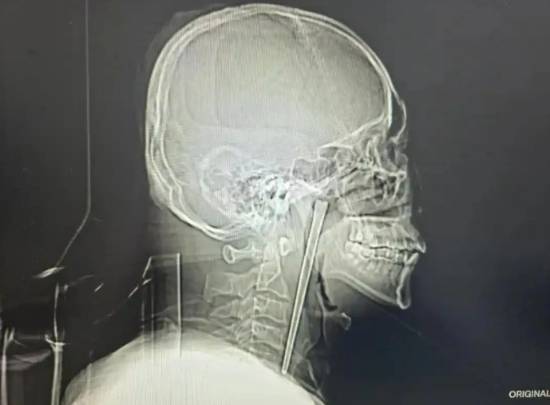

近日,辽宁大连46岁的王先生因咽部突发剧烈疼痛、异物感难忍,前往大连理工大学附属中心医院耳鼻咽喉头颈外科就诊,一项检查结果让医护人员大吃一惊——一根长达12厘米的金属筷子,竟在他的咽部“潜伏”了整整8年之久。有网友留言感叹“真是个狠人,竟然能忍8年”。

接诊的黄巍鹏医生详细询问病史后,立即为王先生安排电子喉镜检查,结果清晰显示,其右侧咽后壁黏膜下、软腭后侧有一根金属筷子嵌入,肉眼可见部分约3厘米。万幸的是,经细致探查,异物邻近的咽部黏膜未出现明显破溃、出血及化脓情况,声带活动正常,喉腔结构也未受到压迫移位,为后续手术创造了良好条件。